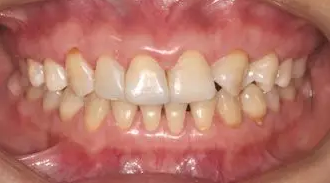

術前微笑照

病例分享|復合樹脂微創(chuàng)美學修復關閉上前牙間隙

術前全牙弓咬合照